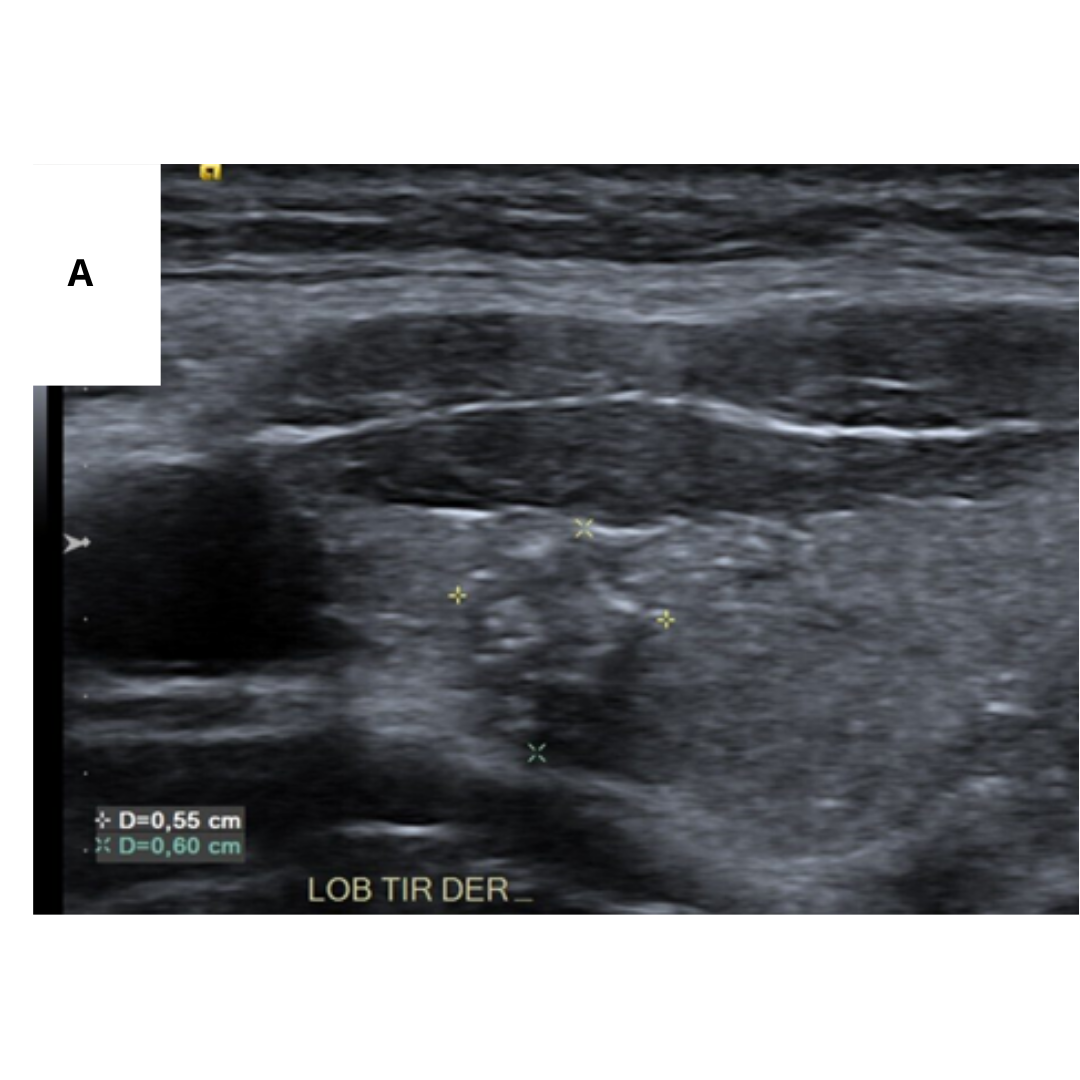

Fig2. A) Masa hipoecoica mal definida, con microcalcificaciones difusas y dispersas que ocupaban toda la glándula. B) Ganglio linfático cervical aumentado de tamaño con múltiples microcalcificaciones dispersas (2).

Fig3. (A) Numerosas microcalcificaciones en todo el lóbulo derecho como una “tormenta de nieve” sin nódulos en la sección longitudinal de la tiroides. (B) Patrón en “tormenta de nieve” en el lóbulo derecho con un nódulo hipoecoico de borde mal delimitado en el corte longitudinal de la tiroides (8).

Fig4. (A) En lóbulo tiroideo derecho, 1/3 medio, se visualiza nódulo sólido, hipoecogénico, mal delimitado con múltiples calcificaciones puntiformes en su interior (cuerpos de Psamoma). (B) Estas también se presentan de manera difusa periféricas al nódulo. (C) En Región cervical derecha, GIV, se visualiza ganglio cervical aumentado de tamaño, con múltiples imágenes puntiformes hiperecogénicos en su periferia e interior sugerente de microcalcifcaciones.